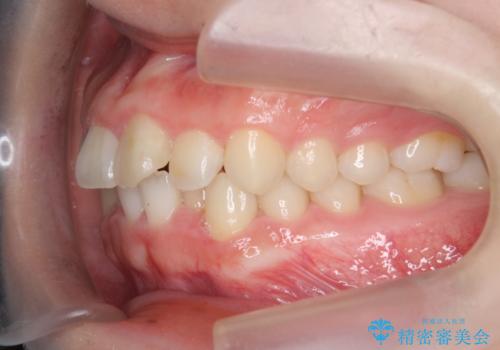

前歯の見た目を改善したい

- ねじれの目立つ前歯の見た目を改善したいと矯正治療を希望され来院されました。

がたつきの改善をマウスピース矯正インビザラインで行っていきます。

ガタつきの改善はもちろん、歯列全体のアーチも放物線状にきれいに排列し審美性を向上させることができました。